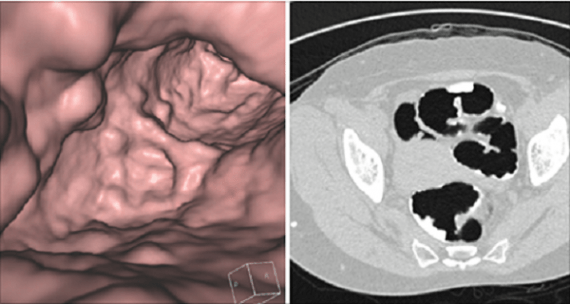

Δεν είναι ακόμη γνωστό αν η εικονική κολονοσκόπηση μπορεί να μειώσει τον αριθμό των θανάτων από καρκίνο του παχέος εντέρου

Τα επίπεδα ακτινοβολίας από μια ενιαία εικονική κολονοσκόπηση είναι παρόμοια με την έκθεση σε ατομικές βόμβες στη Χιροσίμα, αν και σύμφωνα με το Εθνικό Ινστιτούτο Καρκίνου: «Δεν είναι ακόμη γνωστό αν η εικονική κολονοσκόπηση μπορεί να μειώσει τον αριθμό των θανάτων από καρκίνο του παχέος εντέρου».